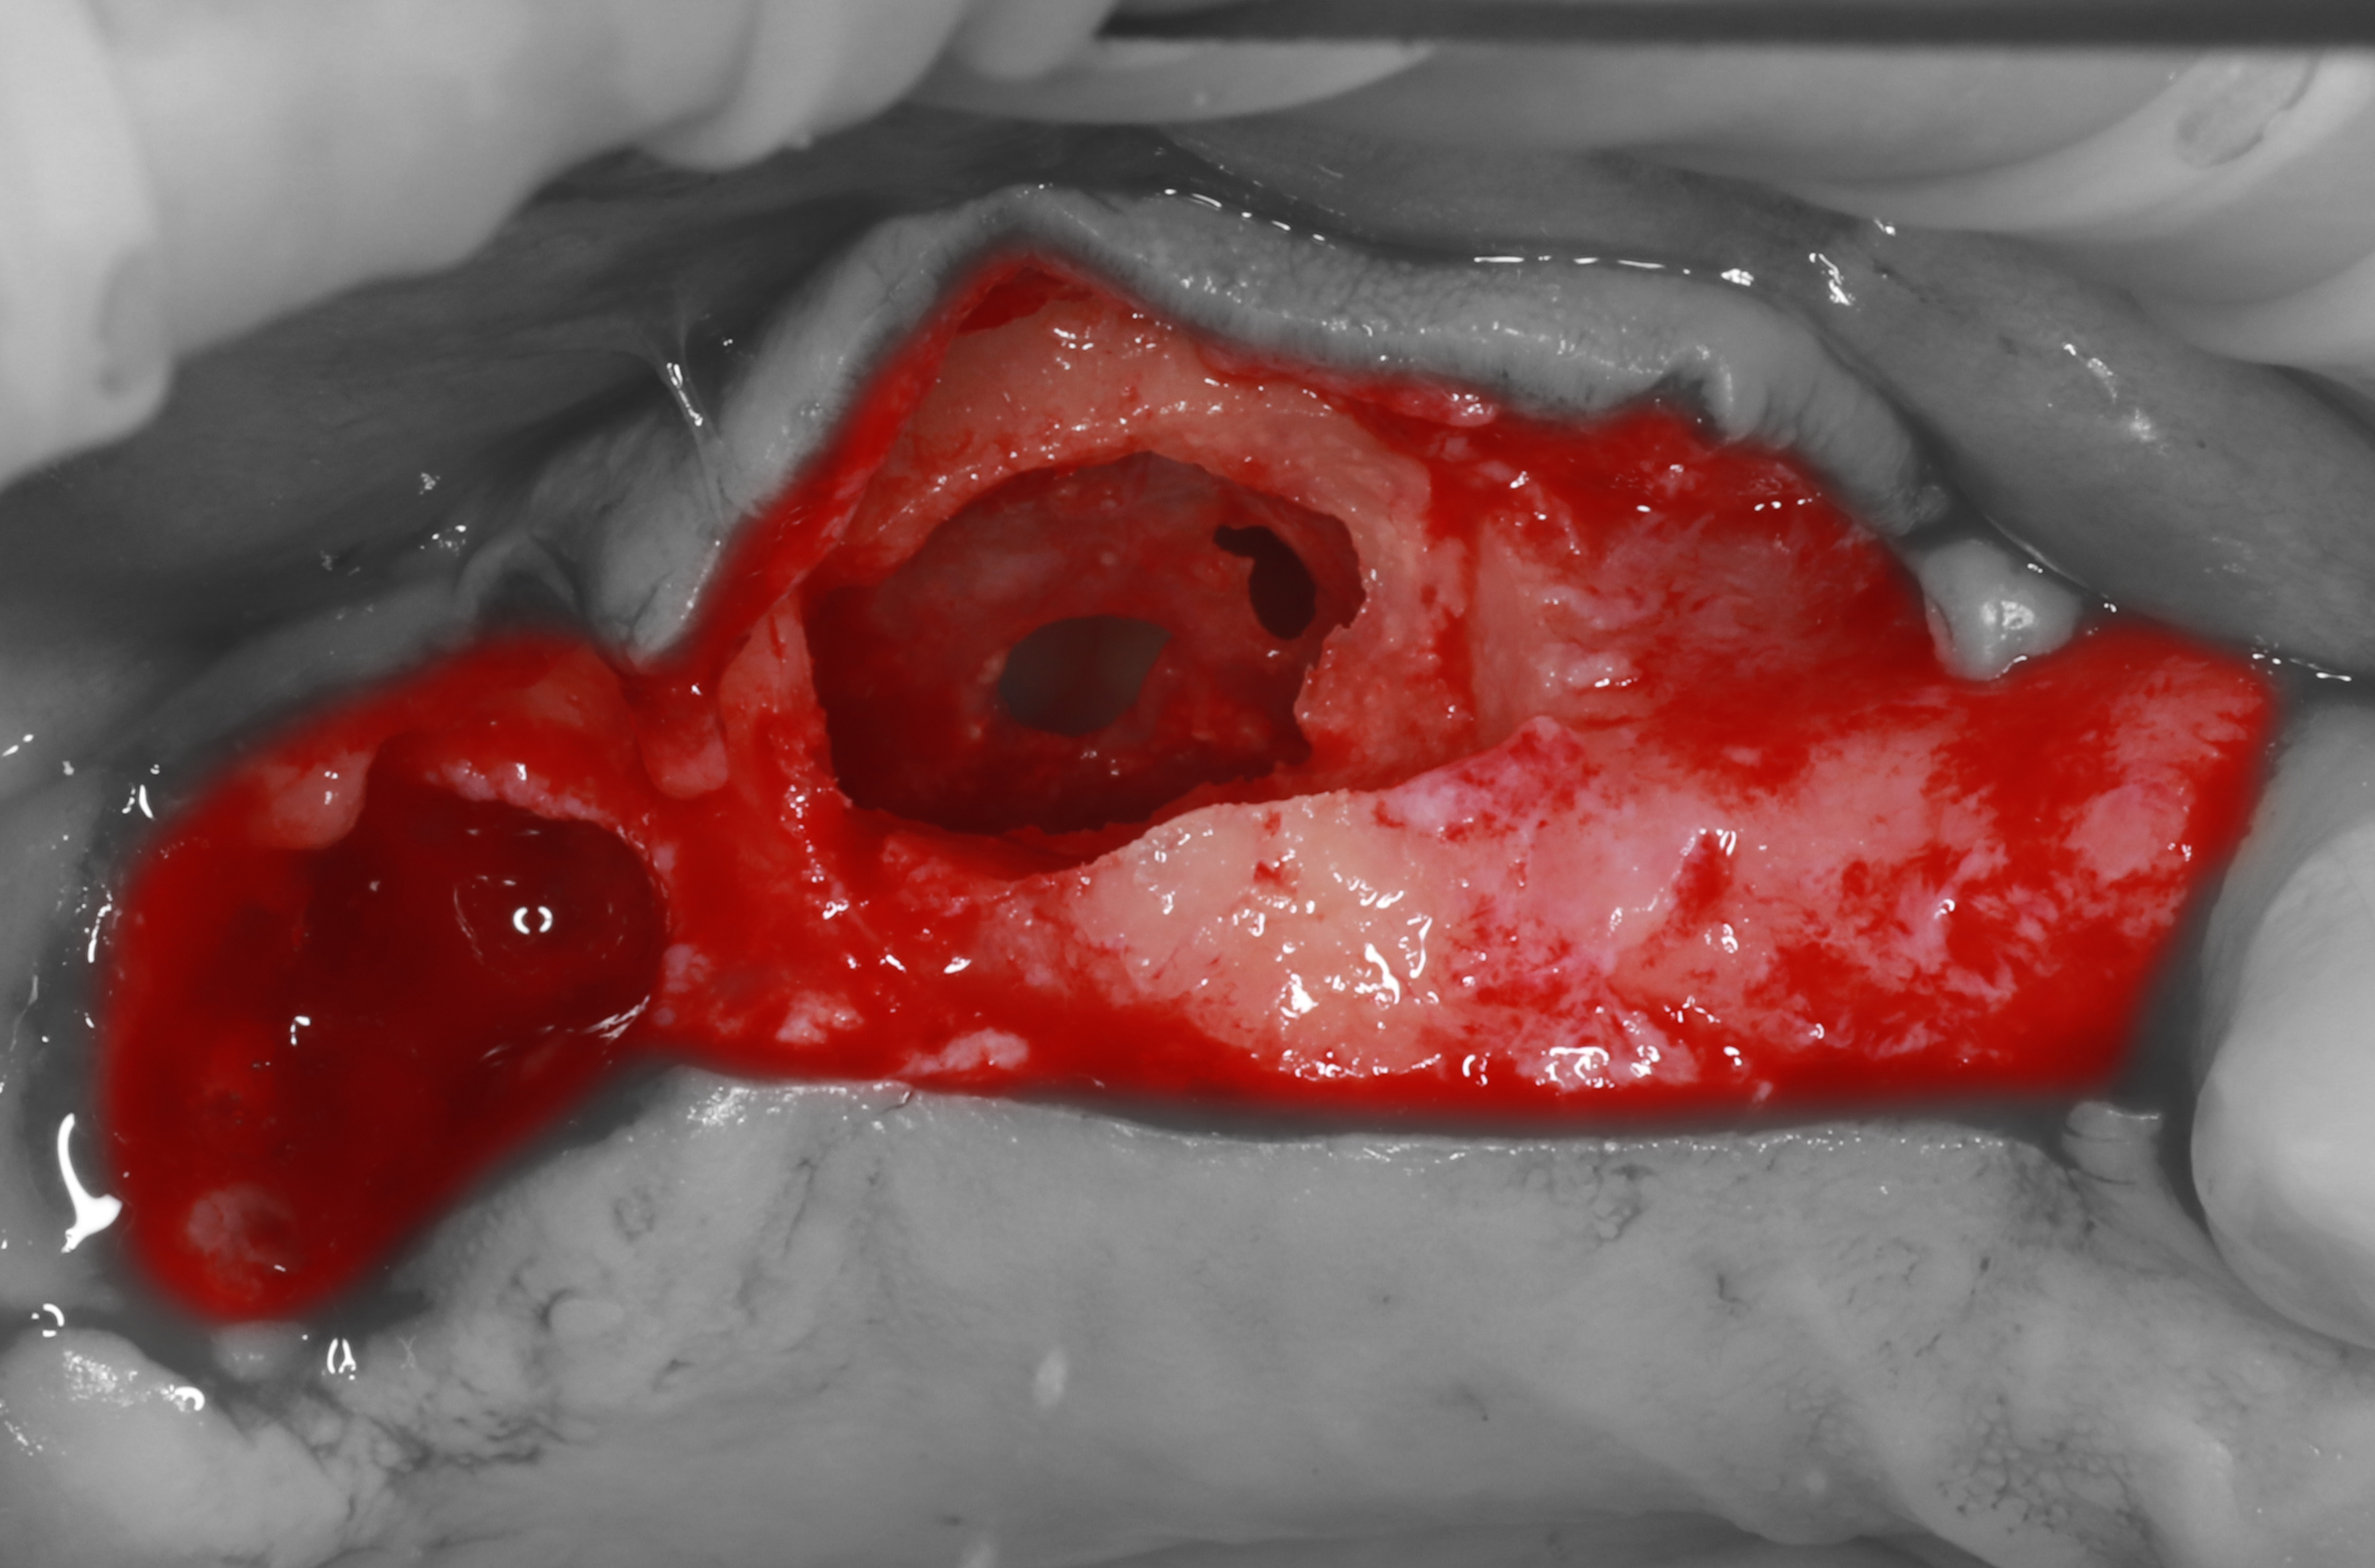

3) С помощью прямого наконечника и алмазной фрезы проведена остеотомия латеральной стенки ВЧ пазухи, с помощью кюрет начато отслаивание Шнайдеровой мембраны.

4) Во время мобилизации слизистой ВЧ синуса были получены перфорации.

5) Проведены остеотомии лож имплантатов, в области ложа имплантата в позиции 2.7 отломалась костная перемычка между остеотомией для синус-лифтинга и имплантата (ошибка: слишком коронарный для субантральной аугментации).